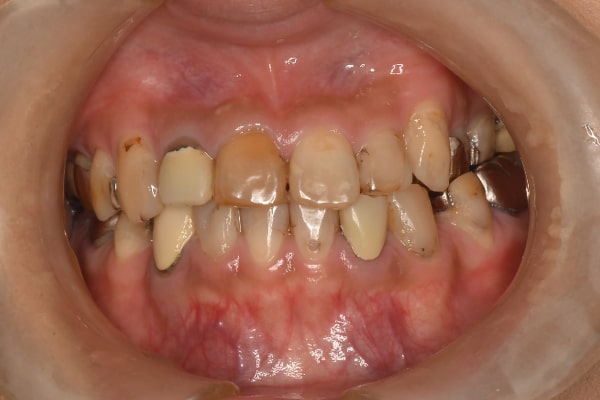

主訴:上の歯を綺麗にしたい(40代女性)

Before